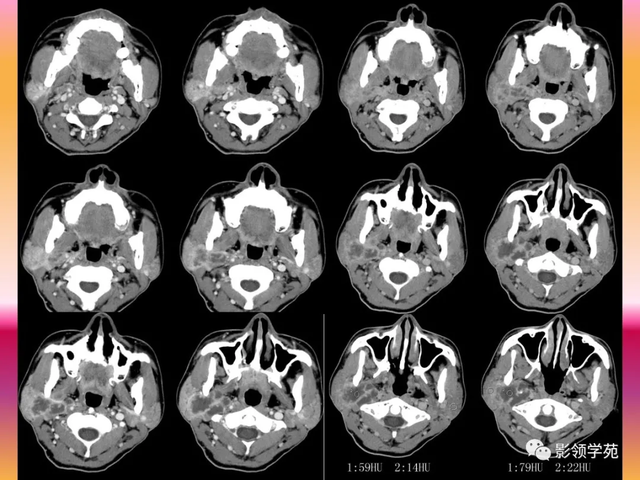

【影像体现】:右侧腮腺不规则增大,边缘强化不规则,CT值为15-44HU,内有低密度坏死区,且见脱离 ,周围显着 强化,未见肿大淋投合。

【影像诊断】:右腮腺脓肿。

2.腮腺脓肿:体现为腮腺局限性肿块并黑点状坏死,典型者可见环状强化,伴相近 筋膜增厚和皮下脂肪层模糊,团结 临床局部皮温升高可诊断。